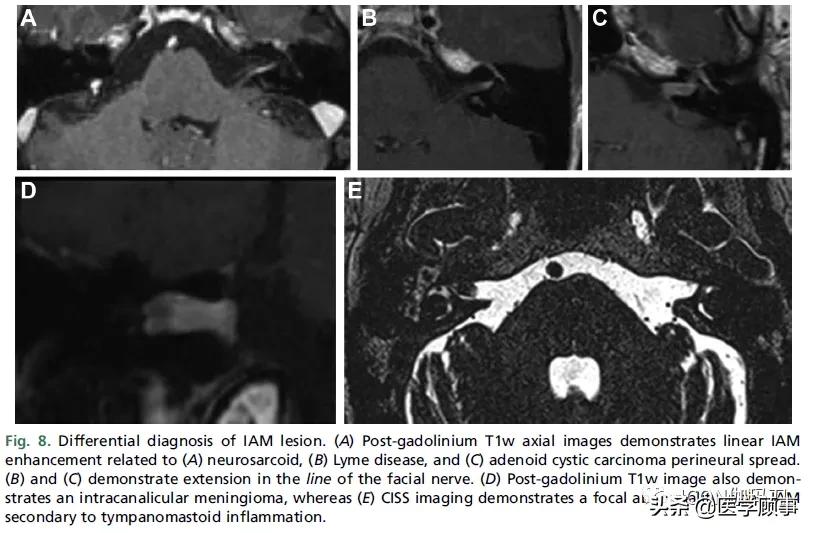

尽管在每个病理学的发生频率方面有差异(图8),内听道(IAM )的VSs的鉴别诊断是类似于那些以桥小脑角为中心的前庭神经鞘瘤(VSs)(参见表3)。首选,统计学上,内听道(IAM)病变在更可能代表前庭神经鞘瘤(VS),神经鞘瘤占所有内听道(IAM)肿瘤的90%以上。最近的一项对在临床和影像学上感觉与前庭神经鞘瘤(VS)相符的内听道(IAM)病变的研究,表明只有2.5%的患者在手术中发现为其他病理。其次,炎性和肿瘤性软脑膜疾病更常表现为内听道(IAM)病变,而不是桥小脑角(CPA)肿块。当考虑内听道(IAM)的炎症和恶性疾病时,无论是炎症性中耳疾病还是来自面神经神经周围播散,在外侧岩骨中寻找病因总是很重要的。

图8。内听道(IAM)病变的鉴别诊断。(A)钆剂后T1w轴位图像显示与(A)神经肉瘤、(B)莱姆病和(C)腺样囊性癌神经周围波散相关的线性IAM增强。(B)和(C)显示面神经线的延伸。(D)钆剂后T1w图像也显示管内脑膜瘤,而(E) CISS图像显示IAM中继发于鼓室瘤样炎症的局灶性异常。